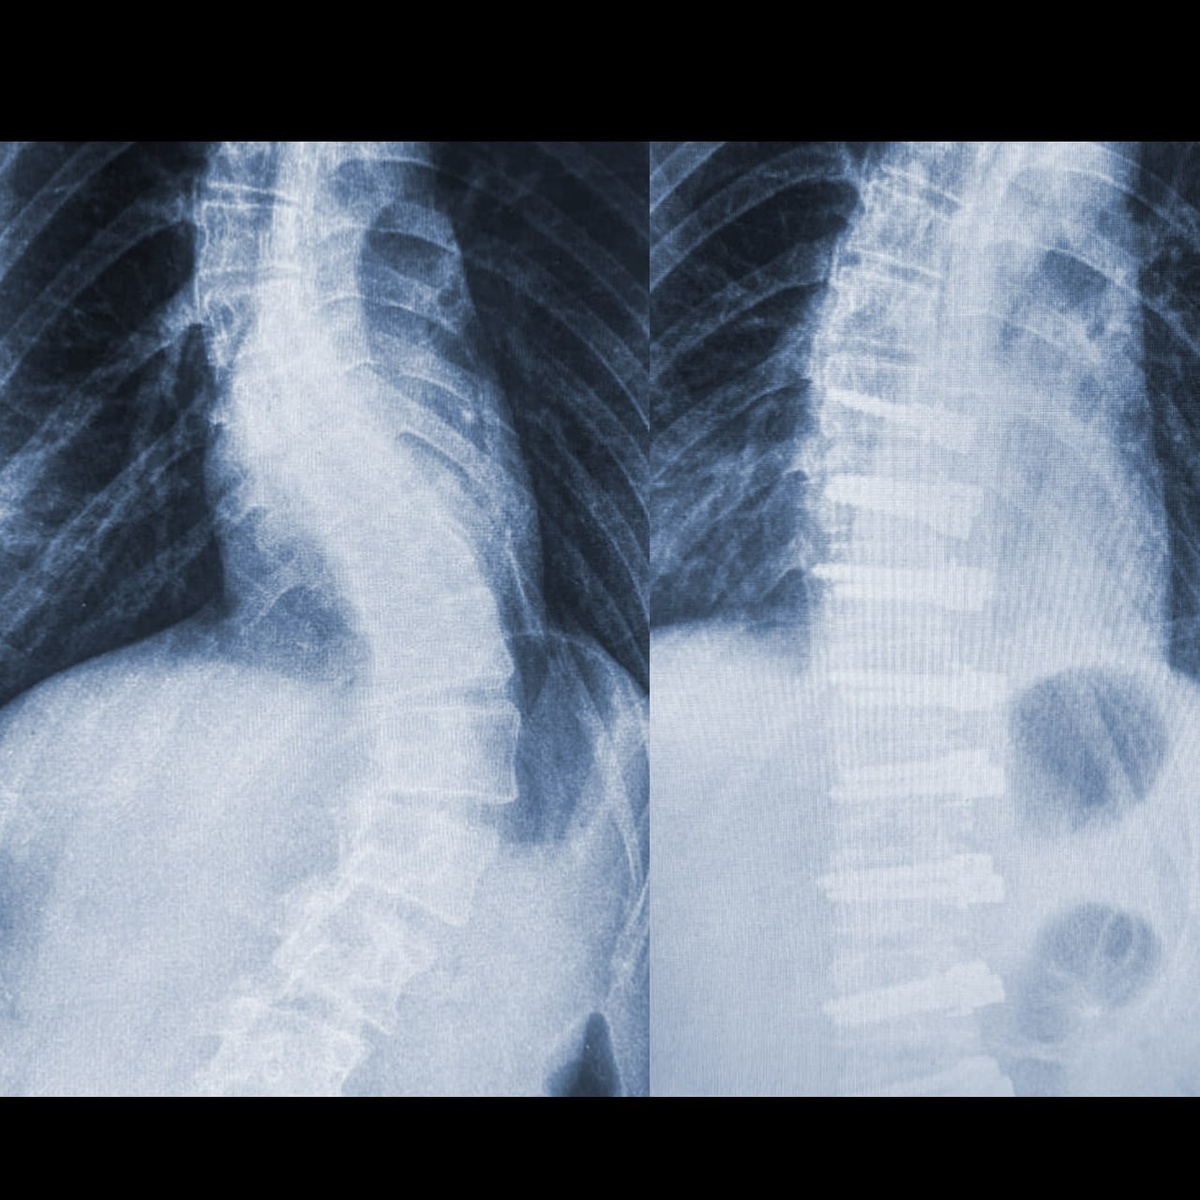

Одной пациентке еще нет 18 лет. Профессор отмечает отличный результат коррекции сколиоза в грудном отделе – «почти в ноль». Совершеннолетней девушке был полностью исправлен грудно-поясничный сколиоз IV степени.

«Вершина деформации расположена в области грудопоясничного перехода и сама деформация достаточно продолжительная. Особенность в том, что чаще всего при операциях с динамической системой достаточно короткая область фиксации, а в данном случае использованы 17 винтов на 10 позвонках с Т7 до L4», - рассказал Сергей Колесов.